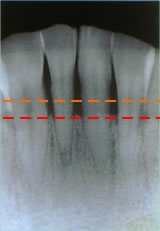

骨(歯槽骨)の状態

- 正常

歯槽骨が正常な位置にあります。

- 中度の歯周炎

歯槽骨の位置が下がってきています。

- 重度の歯周炎

歯槽骨の位置がかなり下がり、

歯の大部分が見えている状態です。